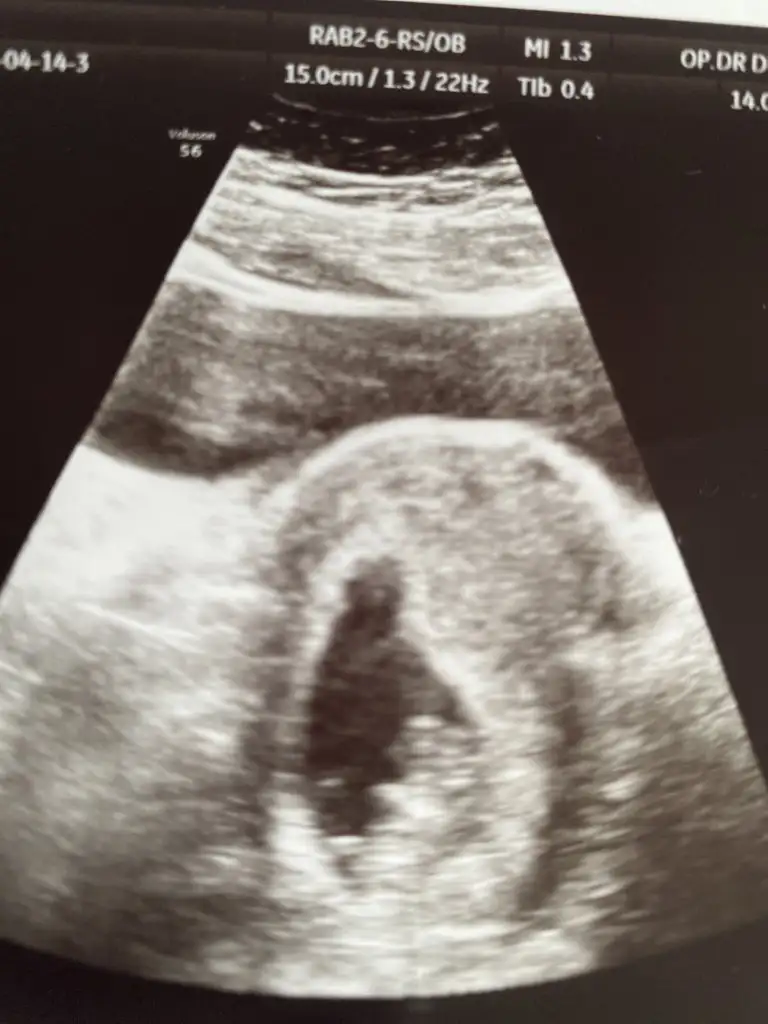

dr soylemeden siz gorun genital nub teorisi ( bebegin cinsiyeti)

Yandan sanki kordon geçmiş eğer arkasındaki nub ise kız gibi sanki pambix pambix